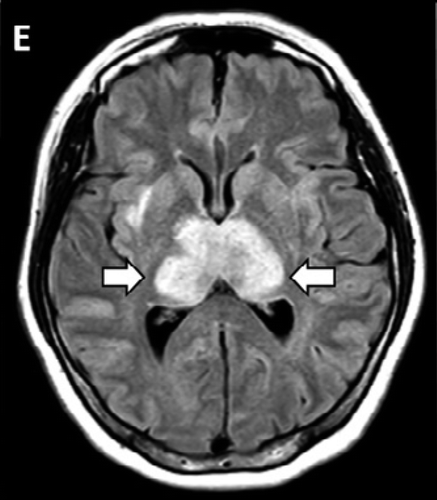

新型コロナウイルスの感染が全世界中で広がるなか、肺炎症状だけでなく、味覚や嗅覚などの異常も報告されるようになったが、米国の研究で、脳の一部で炎症や壊死が進行する「急性壊死性脳炎」を発症していたことが明らかになった。

米ミシガン州デトロイトのヘンリー・フォード・ヘルスシステムの神経科医エリッサ・フォーリー博士らの医療チームが放射線医学誌『ラジオロジー(Radiology)』に先月31日付で発表した症例報告によると、航空会社に勤務する58歳の女性は先月19日、パニック障害や方向感覚の欠如、意識不明などの状態で同病院に救急搬送された。

同時に、頭部のCTスキャン検査を実施したところ、脳の中心部分にあって、視覚や聴覚、運動などをつかさどる「視床」に損傷が見つかり、壊死が起きているのが判明。さらに脳のMRI検査の結果、側頭葉の血管が破裂して出血しているのも見つかった。

当初、急性脳炎を疑っていた医療チームは、免疫機能が暴走して、自身の体にダメージを与える「サイトカインストーム」を起こしていると判断。サイトカインとは、白血球など免疫系の細胞から分泌されるタンパク質で、ウイルスや病原体の増殖を抑えるなどといった役目を果たす。サイトカインストームとは

しかし、免疫系のバランスが乱れて、サイトカインの制御ができなくなると、サイトカインストームといってサイトカインの過剰分泌を起こし、ひどい場合は死に至ることもあるという。

ヘンリー・フォード・ヘルスシステムのチームは「新型コロナウイルスが原因で、急性壊死性出血性脳症を起こした初めての症例だ」として、現場で働く臨床医や放射線医は、この症状の進行に注意するよう呼びかけている。